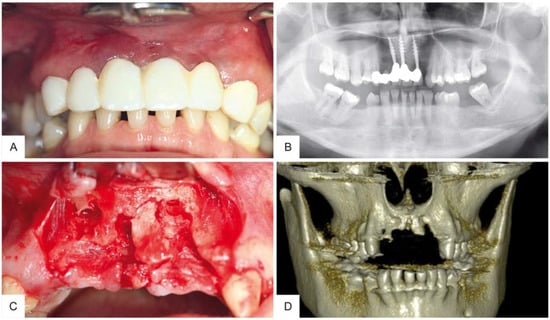

2. Case Report